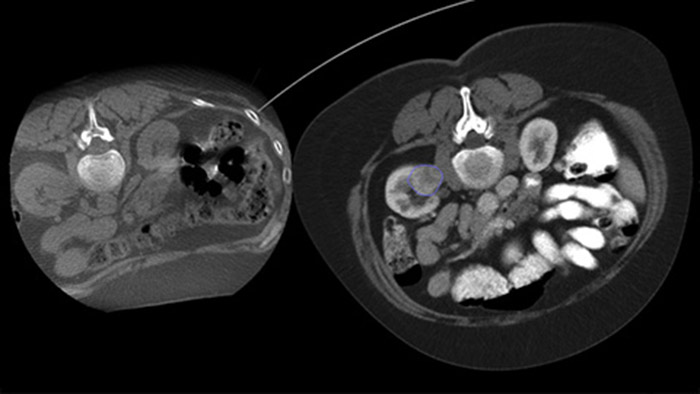

Чрескожная абляция (радиочастотная, микроволновая и криоабляция) — это зарекомендовавший себя малоинвазивный метод лечения опухолей почек, печени, легких и костей. Крайне важно определить границы опухоли, выбрать оптимальное количество игл и соответствующую траекторию для полного лечения опухоли без повреждения окружающих тканей. Прицельное продвижение к поражению при низкой дозе без изменения положения иглы увеличивает шансы на успех и снижает риск осложнений при биопсии или абляции. Проверить результат проведенной абляции можно с помощью 3D-визуализации, пока пациент находится на столе.

Благодаря КТ-подобной визуализации возможно получение КТ-подобных изображений после абляции с целью определения степени охвата опухоли и подтверждения эффективности лечения.

Dual View позволяет наложить 3D-изображение, полученное до процедуры (КТ/МРТ/ПЭТ-КТ), на двойное КТ-подобное 3D-изображение, полученное во время процедуры, для улучшения визуализации поражений и получения важных данных, необходимых для планирования траектории иглы.